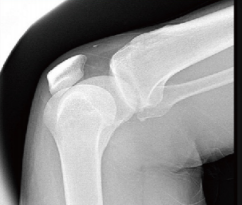

Knee X-Ray